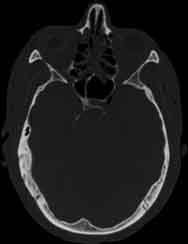

Visible Human male: Sectio transversalis 1116

CT

NMR

Pd T1 T2